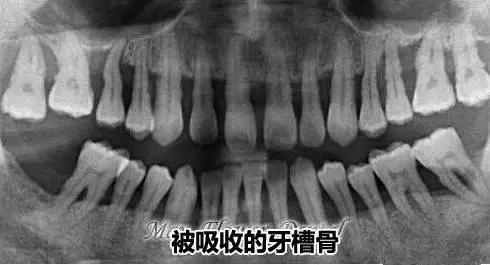

正常的牙槽骨和吸收的牙槽骨**

牙槽骨就是牙根周圍包裹牙齒的組織,如果沒有了牙槽骨,牙齒就像是大樹沒有了土壤,會(hui) 鬆動,掉落。而且多個(ge) 牙齒治療修複項目都需要事先檢查牙槽骨情況是否滿足,比如種植牙,如果牙槽骨骨量少,需要做植骨,滿足條件後才能做進一步操作。

通常全景片不僅(jin) 可以能看到牙槽骨是否存在吸收的情況,還可以在多個(ge) 口腔治療和修複項目中可以起到重要的作用,比如說可以看到是否有恒牙牙胚或者是多生牙的情況,可以看到阻生智齒的位置和方向,確定牙齒不齊的情況,確定種植牙之前判斷牙槽骨的質、量,從(cong) 而確定是否需要植入骨粉。還有根管治療、種牙以及矯治等結果的評估等。